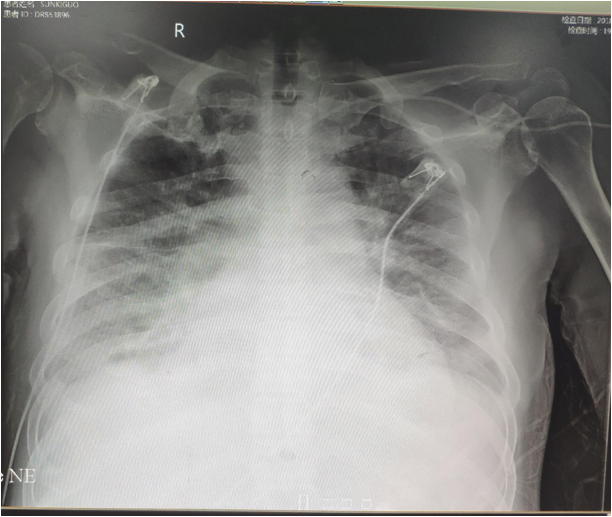

5.27及6.1查胸片示:双肺肺水肿,双侧大量胸腔积液,明显进展

• 06-01行胸腔穿刺引流,提示漏出液,共引流出2000ml胸水